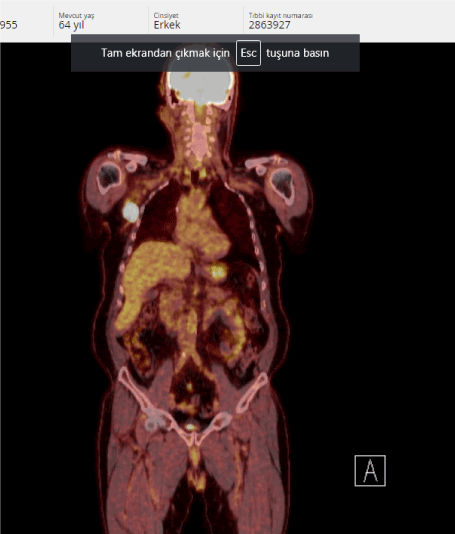

After 3 months of PET/CT, lymphadenopathy of the right axillary region was approximately 4 cm (SUV max. 39.2) (Figures 3 and 4).

Figure 3. Relaps after DCF treatment

Figure 4. Relaps after DCF treatment